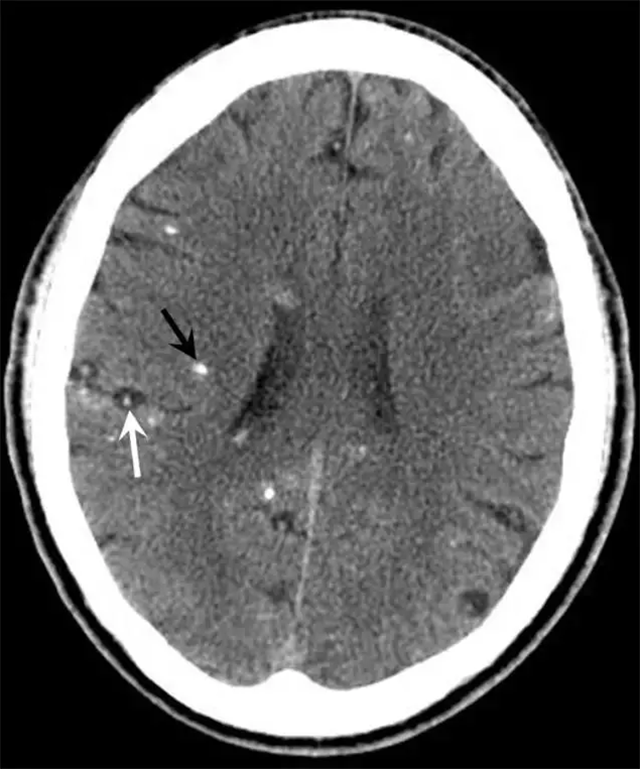

“牛眼征”(白色箭头处)可见于结节肉芽肿期。钙化病灶(黑色箭头处)可见于结节钙化期。